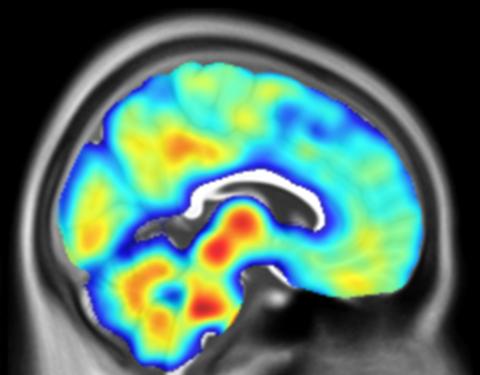

A brain with PSP dementia imaged with PET-TSPO

Malpetti Lab

Using specialist brain scans and novel blood tests to measure inflammation and accelerate the development of new treatments